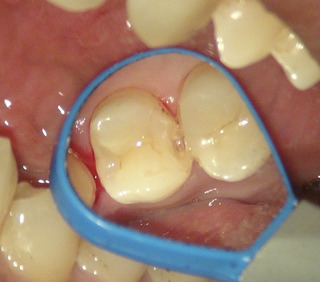

削り始めたら、早速 虫歯で穴が広がっていた

虫歯を染める液で染め出して削る量を最小限に。

水色の部分が虫歯がまだ残っているところ